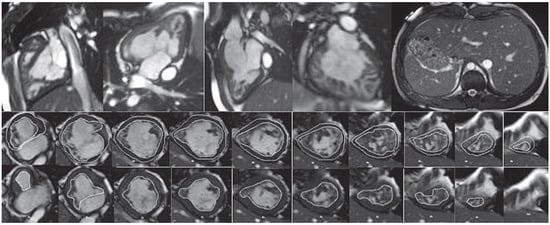

Partial anomalous pulmonary venous connection / sinus venosus defect

| Mandatory | Ventricular volumetry (RV and LV) |

| Cine CMR: axial stack covering all pulmonary venous connections, oblique stack covering anomalous veins, sinus venous defect | |

| CE MRA / 3D SSFP of pulmonary venous return | |

| PC CMR: ascending aorta, MPA | |

| Optional | PC CMR: RPA, LPA, pulmonary veins, SVC above and below anomalous pulmonary veins |

| Cine CMR: oblique coronal stack covering anomalous veins / sinus venosus defect |

Key reporting elements: RV and LV volumes and systolic function, connections and drainage of the pulmonary veins, size of the sinus venosus defect, Qp/Qs (for examples see Figure 5 and Figure 6).

Figure 5.

Uncorrected sinus venosus defect from SVC-type with partial anomalous pulmonary venous drainage (PAPVD) of the right upper pulmonary vein. SSFP cine still frames in axial, oblique and sagittal orientation (A−C), SVC with PAPVD in SSFP cine still frame (D), PC CMR orthogonal en face view of the defect and L−R shunt (black area) (E), CE MRA angiography with visualisation of the the PAPVD (F). * Sinus venosus defect.

Figure 6.

Sinus venosus defect from IVC-type. SSFP cine still frame in coronal, oblique and sagittal views (A−C), inplane PC CMR with black signal of the L−R shunt. * Sinus venosus defect.